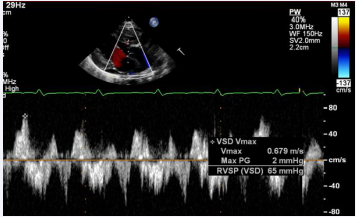

Figure 7 Selected video frames from parasternal long axis views of a neonate with tricuspid atresia with normally related great arteries demonstrating enlarged left atrium (LA) and left ventricle (LV), a small right ventricle (RV), and a moderate-sized ventricular septal defect (VSD; thick arrow) on 2D (A) and color flow (B) imaging. Turbulent flow (B) with a Doppler flow velocity of 2.91 m/s by continuous wave Doppler (C) suggests some restriction of the VSD. Ao, Aorta; PA, pulmonary artery [36].

Figure 7: Selected video frames from parasternal long axis views of a neonate with tricuspid atresia with normally related great arteries demonstrating enlarged left atrium (LA) and left ventricle (LV), a small right ventricle (RV), and a moderate-sized ventricular septal defect (VSD; thick arrow) on 2D (A) and color flow (B) imaging. Turbulent flow (B) with a Doppler flow velocity of 2.91 m/s by continuous wave Doppler (C) suggests some restriction of the VSD. Ao, Aorta; PA, pulmonary artery [36].

The VSD can be demonstrated by 2D (Figure 7A) and the shunt across it by color (Figure 7B), pulsed, and continuous wave (CW) (Figure 7C) Doppler. The peak Doppler flow velocity across the right ventricular outflow tract (RVOT) and pulmonary valve will help in identifying obstruction across these sites. The Doppler data from the VSD and RVOT are helpful in the estimating of pulmonary artery pressures.

As mentioned in a preceding section (Table 1), tricuspid atresia is classified based on the relationship of the great arteries; the most common forms are: Type I, normally related great arteries, and Type II, d-transposition of the great arteries. The great artery relationship is established by following the vessel until bifurcation (Figure 8) or aortic arch. In babies with normally related great arteries the VSD provides blood flow into the lungs. In babies with associated transposition, the VSD provides systemic flow. The VSD may be small, causing obstruction to systemic flow and, therefore, the VSD size should be assessed by 2D (Figures 5, 7A, & 8A) and color (Figures 7B & 9), pulsed (Figure 10), and CW Doppler as necessary.